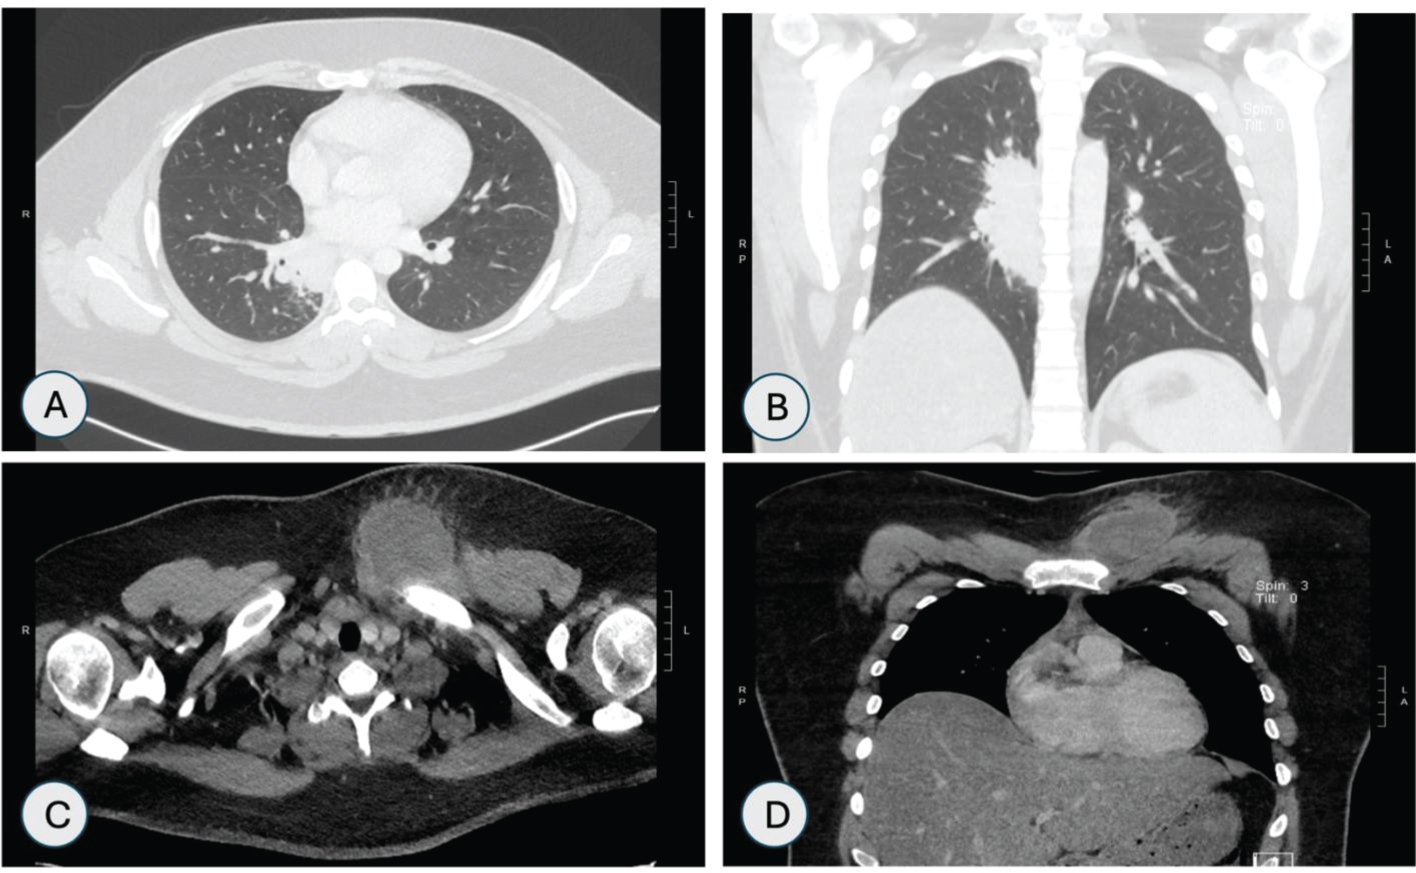

CT scan of chest showed right retrohilar mass measuring 2.3 × 3.6 × 7.7 cm obstructing right lower lobe bronchus and osteomyelitis of left clavicular head along with rim enhancing fluid collection as shown in Figure 4A, Figure 4B, Figure 4C and Figure 4D.

Figure 4: CT Chest-Lung window (A & B) Axial and coronal views showing right retrohilar mass measuring 2.3 × 3.6 × 7.7 cm focally obstructing the bronchus serving the basal medial right lower lobe. CT chest-bone window; (C & D) Axial and coronal views showing lucencies in head of the left clavicle with anterior subcutaneous fluid collection with rim enhancement. View Figure 4

CT head was suggestive of small enhancing lesions in the right frontal cerebral lobe and left cerebellar hemisphere (Figure 5A). Magnetic resonance imaging (MRI) of head showed multiple small enhancing foci in bilateral cerebral and cerebellar hemispheres as shown in Figure 5B. MRI of left knee showed enhancement in the medial tibial epiphysis and metaphysis with adjacent soft tissue edema and large suprapatellar effusion (Figure 5C).

Figure 5: (A) CT head showing 5 mm enhancing lesion in left cerebeller hemisphere; (B) MRI head showing multiple enhancing foci in bilateral cerebral hemispheres; (C) MRI left knee showing large suprapateller effusion. View Figure 5